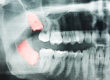

Wisdom teeth can cause a number of issues for Dallas TX patients. Because there is no longer room in the jaw to accommodate the wisdom teeth, they often become impacted. When the wisdom teeth fail to erupt or do so only partially, they can develop tumors or cysts.

It’s best to have your wisdom teeth removed before age 25 because the roots are shorter and can be more easily removed. As patients get older, the wisdom teeth become more entrenched in the jawbone and the extraction surgery becomes more complex.